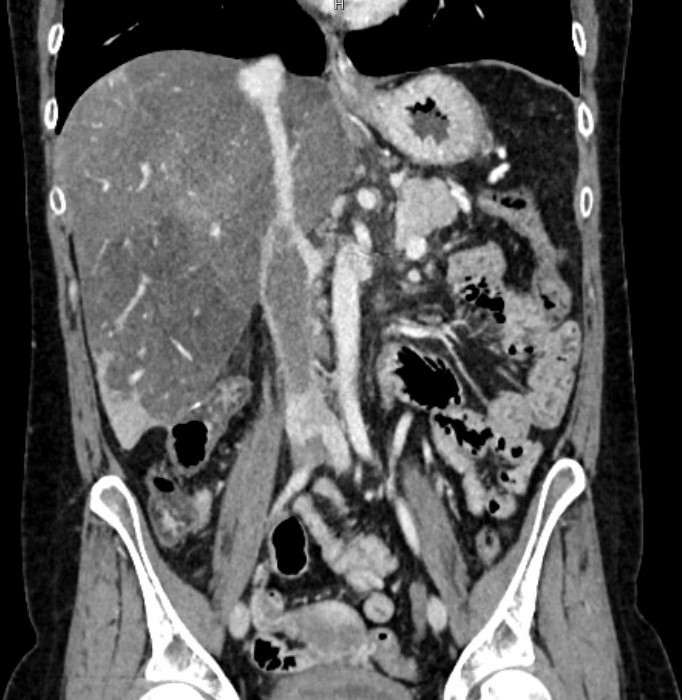

- Imaging of the abdomen and pelvis – Including CT venogram (most common) or MR venogram or sometimes venography.